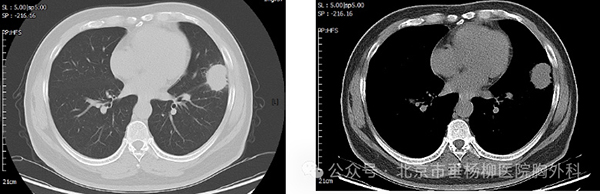

患者,男性,50岁,主因“发现左肺上叶占位性病变2月余。”来诊。患者自诉2月前体检胸部CT,发现左肺上叶舌段实性占位,大小约2.5*2.3cm,与胸膜相连,可见分叶、毛刺,恶性可能性大,有咳嗽、咳痰,白痰为主,偶有黄痰,无痰中带血等异常,未采取治疗,定期复查。2周前再次复查胸部ct:左肺上叶占位性病变较前增大,侵犯下叶背段,大小约4.1*3.1cm,考虑肺癌可能。

术前胸部CT-肺窗 纵隔窗